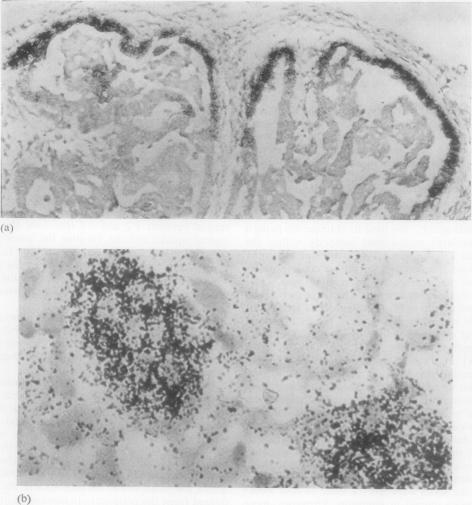

The use of monoclonal antibodies which can be raised to antigens of choice offers a selective and specific approach for the detection of tumours both in vivo and at a cellular level in biopsy specimens. We demonstrate that a monoclonal antibody raised to human teratoma will localise in a teratoma, growing as a xenograft in immune-suppressed mice.

能够针对选定抗原产生的单克隆抗体,为在体内和活检标本的细胞水平上检测肿瘤提供了一种选择性和特异性的方法。我们证明,一种针对人畸胎瘤产生的单克隆抗体将定位在作为异种移植瘤生长于免疫抑制小鼠体内的畸胎瘤中。